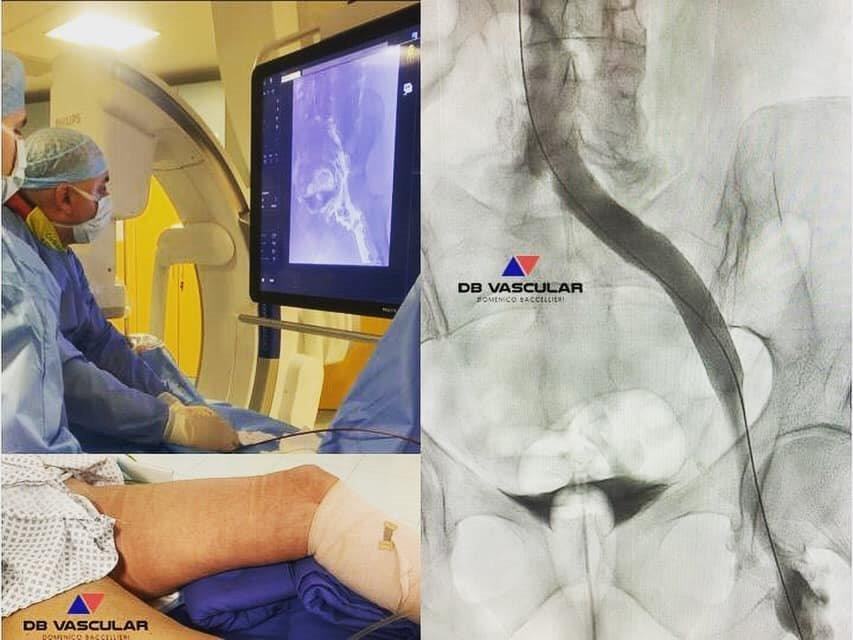

In pochissimo tempo, durante un ecocolordopler, mi dice con fermezza e professionalità che ho una sindrome denominata MAY THURNER, che mi avrebbe aiutato a risolvere i miei problemi, intervenendo d’urgenza con due interventi delicati; da subito mi sono sentita al sicuro e protetta.

“Con il primo intervento è stato ricanalizzato e impiantato uno stent nella vena iliaca comune esterna, e con il secondo, impiantando un secondo stent, nella vena iliaca comune sinistra, entrambe interventi in anestesia generale. Da subito tutti i circoli collaterali sono scomparsi e sono tornata a sentire la gamba, di nuovo, leggera”.

“La sindrome di May-Thurner (MTS) è una condizione patologica relativamente rara, scoperta negli anni ’50, causata da un difetto anatomico. La vena iliaca comune di sinistra è compressa fra l’arteria iliaca comune destra e la colonna vertebrale lombare inferiore, con conseguente processo di ostruzione meccanica. La compressione cronica da parte di una grossa arteria pulsante contro una superficie ossea crea un danno endoteliale a carico della parete della vena. La conseguente fibrosi causa una ostruzione meccanica fissa che determina sia stasi venosa cronica, sia una predisposizione per il processo trombotico. La MTS può essere inoltre una delle cause della congestione pelvica.”